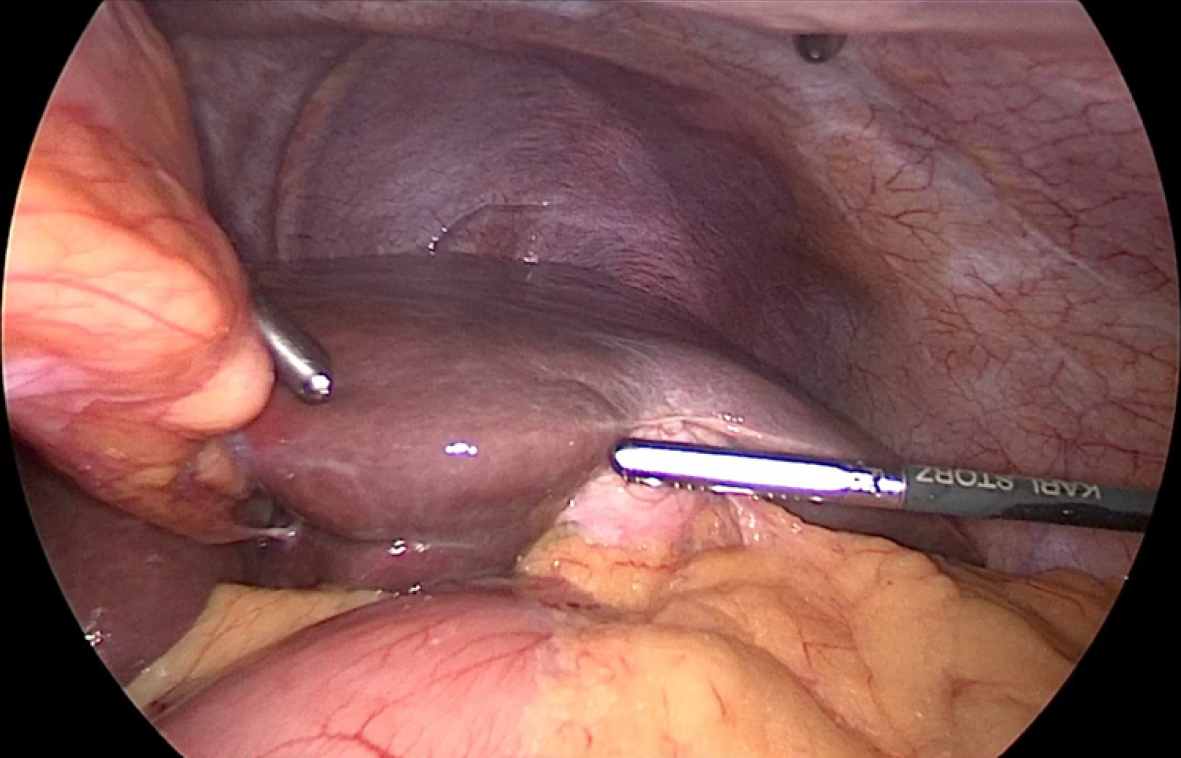

Both patients underwent elective laparoscopic cholecystectomy using a mirror-image four-port configuration (Figure 5). In both cases, the critical view of safety was achieved prior to division of the cystic duct and artery. Intraoperative findings confirmed left-sided gallbladder anatomy (Figure 6A). Dissection was carried out with careful orientation to Rouvier’s sulcus, and the critical view of safety was achieved before division of the cystic duct and artery (Figure 6B and C). The gallbladder was retrieved through the epigastric port (Figure 6D).